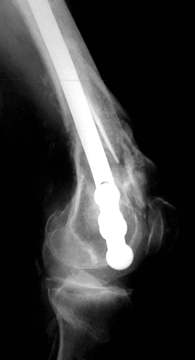

Stabilisierung der Fraktur auf der rechten Seite bei der gleichen Patientin

Bereits 8 Tage nach der Operation konnte die Patientin die Knie auf über 90° beugen.